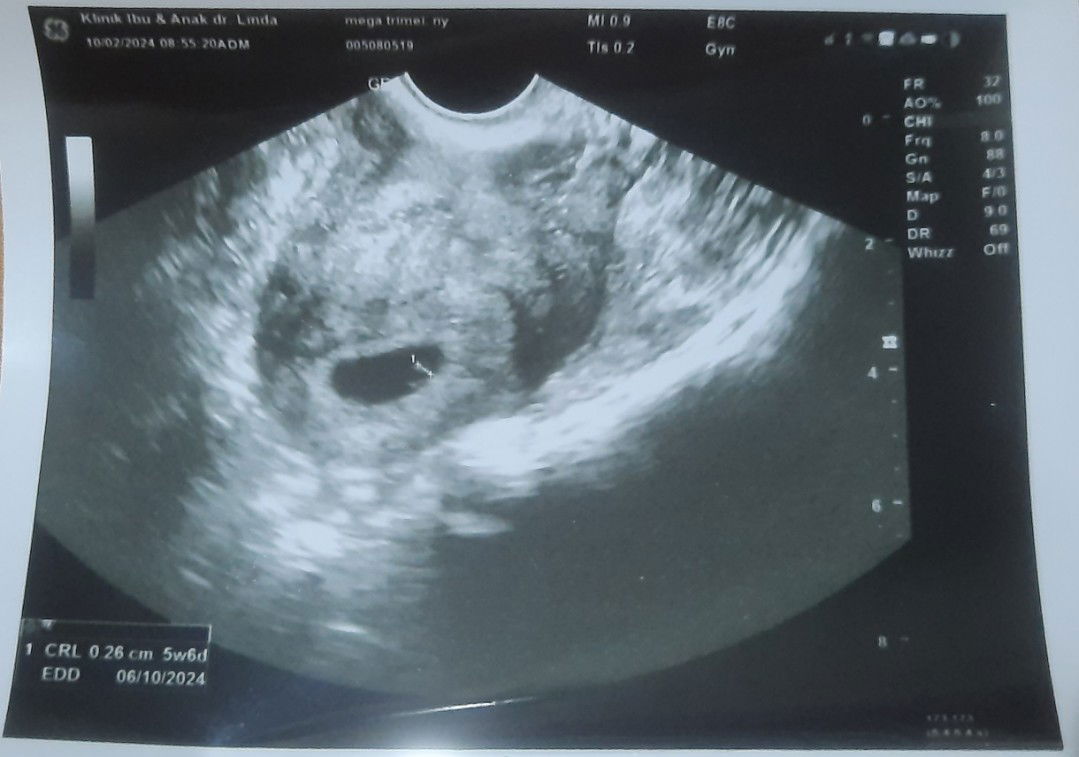

Umur dr hasil usg 2d dan usg transvaginal berbeda

Bunda² cantik mohon informasinya yaaa, sy hpht 5 januari kalau menurut hasil hasil usg 2d dan perhitungan aplikasi/manual ada di umur 5w perkiraan lahir 11 okt. Td sy usg transvaginal ada di usia 5w6d perkiraan lahir 6 okt. Menurut bunda² akurat yg mana ya ?